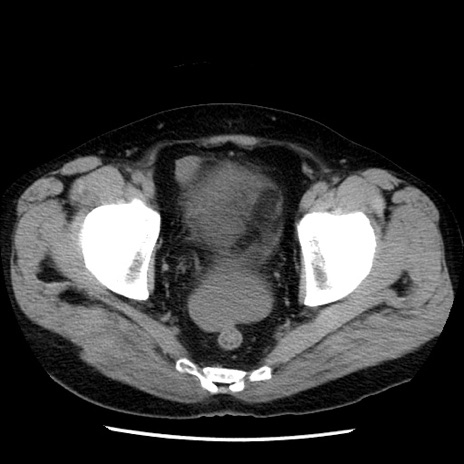

症例29(横断像)

【症例】40歳代男性

【現病歴】2日前から胃痛あり。徐々に周期的な激痛に変化した。本日になっても激痛があるため受診。

【身体所見】意識清明、BT 38-39℃台あり、腹部:膨満、やや硬、右下腹部に圧痛あり。

【データ】WBC 8500、CRP 23.26